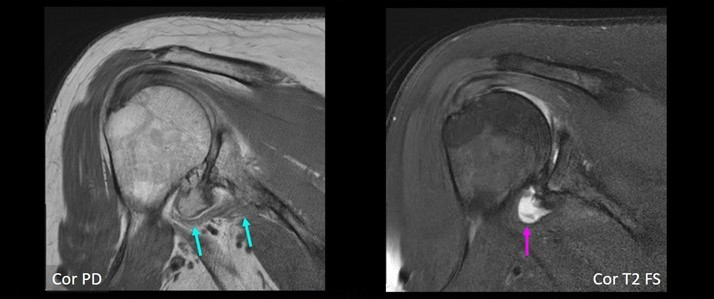

66-year-old female with severe shoulder pain. Coronal MR images show definite small AIGM (blue arrows), corresponding to diagnostic confidence of 4. In addition, there is high-grade glenohumeral osteoarthrosis, as well as small joint effusion (purple arrow).